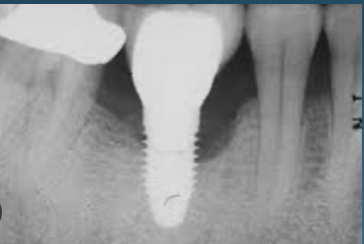

(1.) Peri-implantitis bone loss.

Figure 1

(2.) Peri-implantitis bone loss.

Figure 2

Peri-implantitis is defined as a bacterial plaque-associated pathological condition related to oral biofilm occurring in tissues around dental implants, characterized by inflammation in the peri-implant mucosa and subsequent progressive loss of surrounding bone1-8(Figure 1 and Figure 2). Food impaction is a contributing but not a primary factor in the disease process.